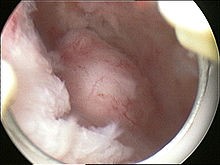

A relatively large submucosal leiomyoma; it fills out the major part of the endometrial cavity |

submucosal fibroid in hysteroscopy |